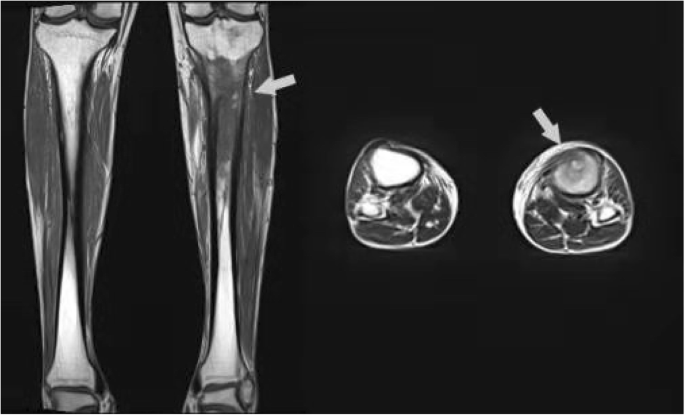

Once admitted to the inpatient department, all of patients were suggested to receive physical examinations, X-rays, and laboratory tests. For patients without implants, preoperative MRI examination was accomplished in the following days for determining the extent of infection (Fig. 1). Empirical antibiotic administration was not started until samples had been obtained for culture during surgery. Preoperative laboratory results showed, mean erythrocyte sedimentation rate (ESR) 23.22 mm/h, mean C-reactive protein (CRP) level 3.41 mg/L, and mean white blood cell (WBC) 6.71 × 109/L. Intra-operative topical antibiotics of those cases included both vancomycin and gentamicin, in order to cover both Gram-positive and negative bacteria.